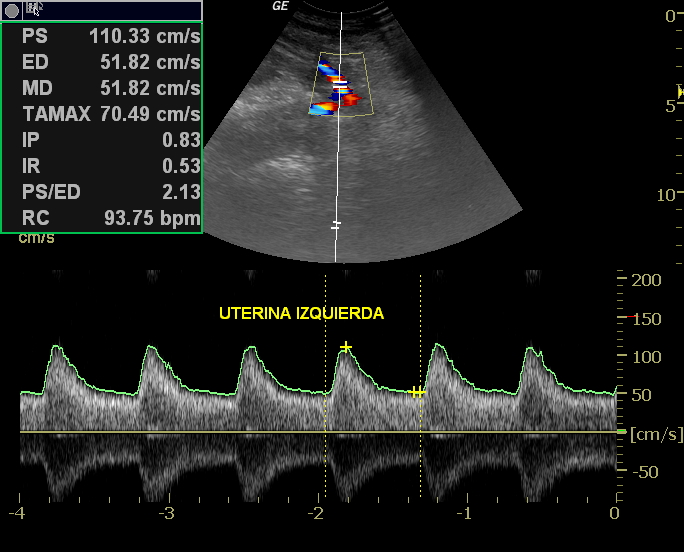

Algunos de los marcadores y estructuras que valoramos durante este estudio están: el pliegue Nucal, Hueso nasal, 5to dedo trifalángico, Ductus Venoso, descarte de insuficiencia tricuspidea, estructuras del Cordón umbilical, Columna Vertebral, Valoración sistematica y detallada del sistema nervioso Central, Extremidades, descarte de patológicas morfológicas o estructurales, confirmación del Sexo Fetal, valoración de pies y manos, descarte de labio leporino y/o hendidura palatina, valoración del Líquido amniótico, placenta, Orificio Cervical interno, Arterias Uterinas maternas, entre otros parámetros no menos importantes.